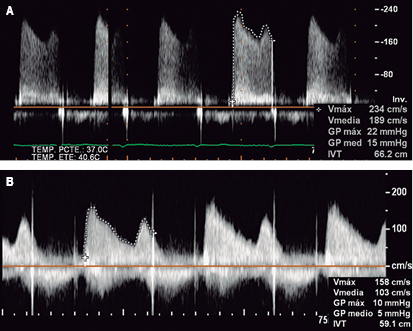

Transthoracic and transesophageal echocardiography: left ventricular end-diastolic volume of 45 milliliters, systolic volume of 11 milliliters, ejection fraction 76%, without changes in global or segmental mobility at rest, without thrombi, with concentric remodeling data; dilated left atrium without thrombi, a left atrial volume index (LAVI) 48 mL/m2 is calculated; mitral valve bio-prosthesis thickened, heavily calcified, irregular by pannus (Figure 3), with inadequate excursion and closure, with one of the leaflets fixed (Figure 4), an acceleration of flow rate 2.9 m/s, it shows maximum peak velocity of 2.9 m/s with maximum gradient of 34 mmHg and mean gradient of 25 mmHg (Figure 5), valve area by continuity 0.5 cm2, indexed 0.3 cm/m2, by pressure half-time of 0.7 cm2, with mild central regurgitation jet, Doppler index of 4; aortic valve bio-prosthesis with mild calcification, with suitable excursion and closing, maximum peak velocity of 2.2 m/s, maximum gradient 29 mmHg, mean gradient 15 mmHg, valve area by continuity 1.3 cm2, indexed 0.81 cm/m2, with no evidence of leakage, a Doppler index of 0.28; right ventricle: dilated, hypertrophic, with preserved systolic function, tricuspid annular plane systolic excursion (TAPSE) 17 mm/m2, S wave 12 cm/s; right atrium: dilated, without thrombi; tricuspid valve: structurally normal, deficient coaptation, with a concentric regurgitation jet generating severe failure, vena contracta 10 mm, regurgitation area 16 cm2, a systolic pulmonary artery pressure (SPAP) of 105 mmHg is calculated.

Held on January 22, 2016, prior informed consent of the patient and family. Under general anesthesia with endotracheal intubation, it proceeds to perform asepsis and antisepsis of both femoral regions, with modified Seldinger technique are punctured left femoral artery and right femoral vein, placing introducers of 5 and 6 French (fr), temporary pacemaker is placed in the right ventricle without complications and adequate capture is confirmed, remaining on guard. Then, a left anterolateral thoracotomy is performed at the fifth intercostal space, the pericardium is incised longitudinally and marsupialized, tucks are placed in snuff bag form with prolene 2-0 to expose the left ventricular apex without penetrating ventricular cavity, near the apex and lateral to the anterior descending artery with modified Seldinger technique the apex is punctured at the level of the left ventricle and the femoral introducer 6 fr is advanced, the mitral bio-prosthetic valve is intersected with a 0.035 mm teflonated guidewire with interchange curve, the multipurpose catheter 1.5 fr is advanced through which a guide "Amplatz extra-stiff" is swapped to the left pulmonary vein (Figure 6), introducer Ascendra of 24 fr is placed and through this the delivery transapical system with an Edwards Sapien #26 (Edwards Lifesciences, Irvine, California) valve, after corroborating the proper position with fluoroscopy in right anterior oblique projection, the valve is released successfully (Figure 7). Transesophageal echocardiography performed during the procedure shows the dysfunctional prosthetic mitral valve with a mean gradient of 25 mmHg, the apex is located for the surgical intervention, and is verified in two and four cameras projection, coaxiality with needle and introducer is verified, biological prosthetic valve is intersected with guide and introducer, the deployment of percutaneous mitral valve on longitudinal axis of 3 cameras (120o) is monitored, and the proper position of the valve is verified, without identifying paravalvular leak, appropriate opening/closure and mean gradient of 3 mmHg (Figure 8). Introductors and delivery system are removed, the apex is closed by knotting the two sutures in bag snuff previously set, a pericardial effusion was shown by transgastrical projection, restricted exclusively to posterior wall without hemodynamic effects on right cavities, monitoring is performed by subcostal window observing a separation of sheets of 15mm, repair apex was performed with prolene 2-0 due to a left ventricle tear, contained without further complication; pericardium and chest wall is closed in layers, prior echocardiography subcostal drain is placed, and pacemaker is maintained with stimulation. Fluoroscopy time of 24 minutes, use of 22 milliliters of contrast, removing introducers and considering the procedure as successful.

The patient was transferred to an intensive coronary care unit, in which courses without immediate complications, with the support of norepinephrine and mechanical ventilation; is extubated within 24 hours and vasoactive amines are removed within 48 hours of the procedure, within 72 hours pacemaker is removed, remaining in sinus rhythm and with adequate heart rate without requiring the placement of a definitive device, removing the subcostal drain subcostal prior assessment of cardiothoracic surgeon. It was decided to continue hospitalization for 5 days due to lower respiratory tract infection, improving to remission. The hospital discharge is decided on January 2016, to continue outpatient follow-up, referring the patient in NYHA functional class I. After 6 months follow-up remains in NYHA functional class I. Transesophageal echocardiogram reported a non-dilated left ventricle with ejection fraction of 70%; dilated left atrium with LAVI of 39 mL/cm2; non-dilated right ventricle with normal rest wall thickening, TAPSE 21; normofuncional percutaneous mitral prosthesis in adequate position (within bio-prosthesis) with maximum peak velocity of 1.6 m/s, maximum gradient 10 mmHg, mean gradient to 5 mmHg, valve area of 1.7 cm2, without paravalvular leakage (Figure 5); structurally normal tricuspid valve without stenosis, lack of coaptation of the cusps that conditions mild regurgitation; structurally normal pulmonary valve without significant gradients, SPAP 60 mmHg.